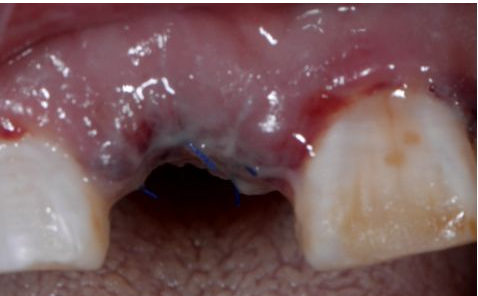

植入后縫合

術(shù)后三天

在口腔種植領(lǐng)域中,由于各種原因造成的種植牙局部牙槽突骨量不足或種植體周圍骨缺損的修復(fù)在種植外科的研究中已經(jīng)取得了重大突破。新一代的血漿提取物--濃縮生長因子(CGF,Concentrate Growth Factors)能夠明顯縮短術(shù)區(qū)成骨的時間,提高成骨質(zhì)量,促進(jìn)成骨及組織的愈合;具體有:引導(dǎo)骨再生技術(shù)、聯(lián)合骨膜表面覆蓋加速軟組織愈合、用于上頜竇提升、拔牙后即刻種植、牙槽嵴位點(diǎn)保存、頜骨囊腫的治療、牙槽骨修整。